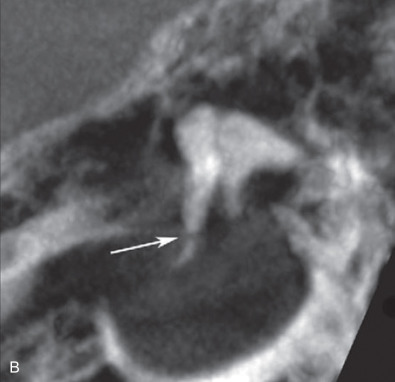

Ossicular fracture is more unusual. Tailored multiplanar reconstructions (MPRs) coupled with even higher-resolution techniques like flat-panel CT allow the neuroradiologist and otolaryngologist to visualize the entire ossicular chain to localize damage ( Fig. 1.17.3 ).

Middle ear exploration can be offered in cases of persistent CHL and if hearing is not severely impaired in the contralateral ear. The ideal time to explore is unknown. Early intervention may be premature; however, the longer one waits, the greater likelihood of ossicular chain fixation. Outcomes for surgical repair are good, with most patients improving by 20 dB to near or normal hearing levels.